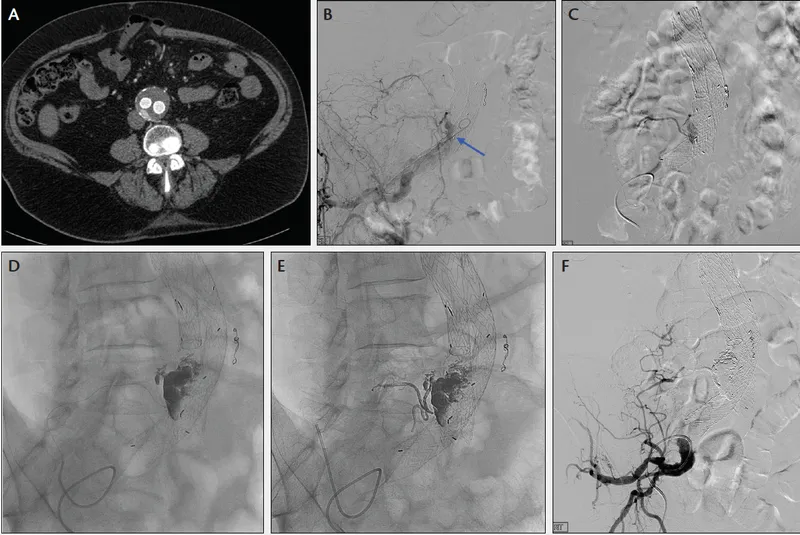

- Pre-op Planning (Gold Standard): CT Angiography (CTA).

- Defines anatomy: diameter, length, neck morphology, renal/iliac artery involvement.

| Approach | Midline laparotomy, aortic cross-clamp, sutured graft | Percutaneous femoral access, deployed stent-graft |

⭐ > EVAR's primary long-term complication is endoleak: persistent blood flow into the aneurysm sac outside the stent-graft. Type II is most common (from lumbar/IMA back-bleeding) and often observed. Type I (inadequate seal) requires urgent intervention.

- EVAR-Specific: Endoleak (persistent blood flow into aneurysm sac), graft migration.